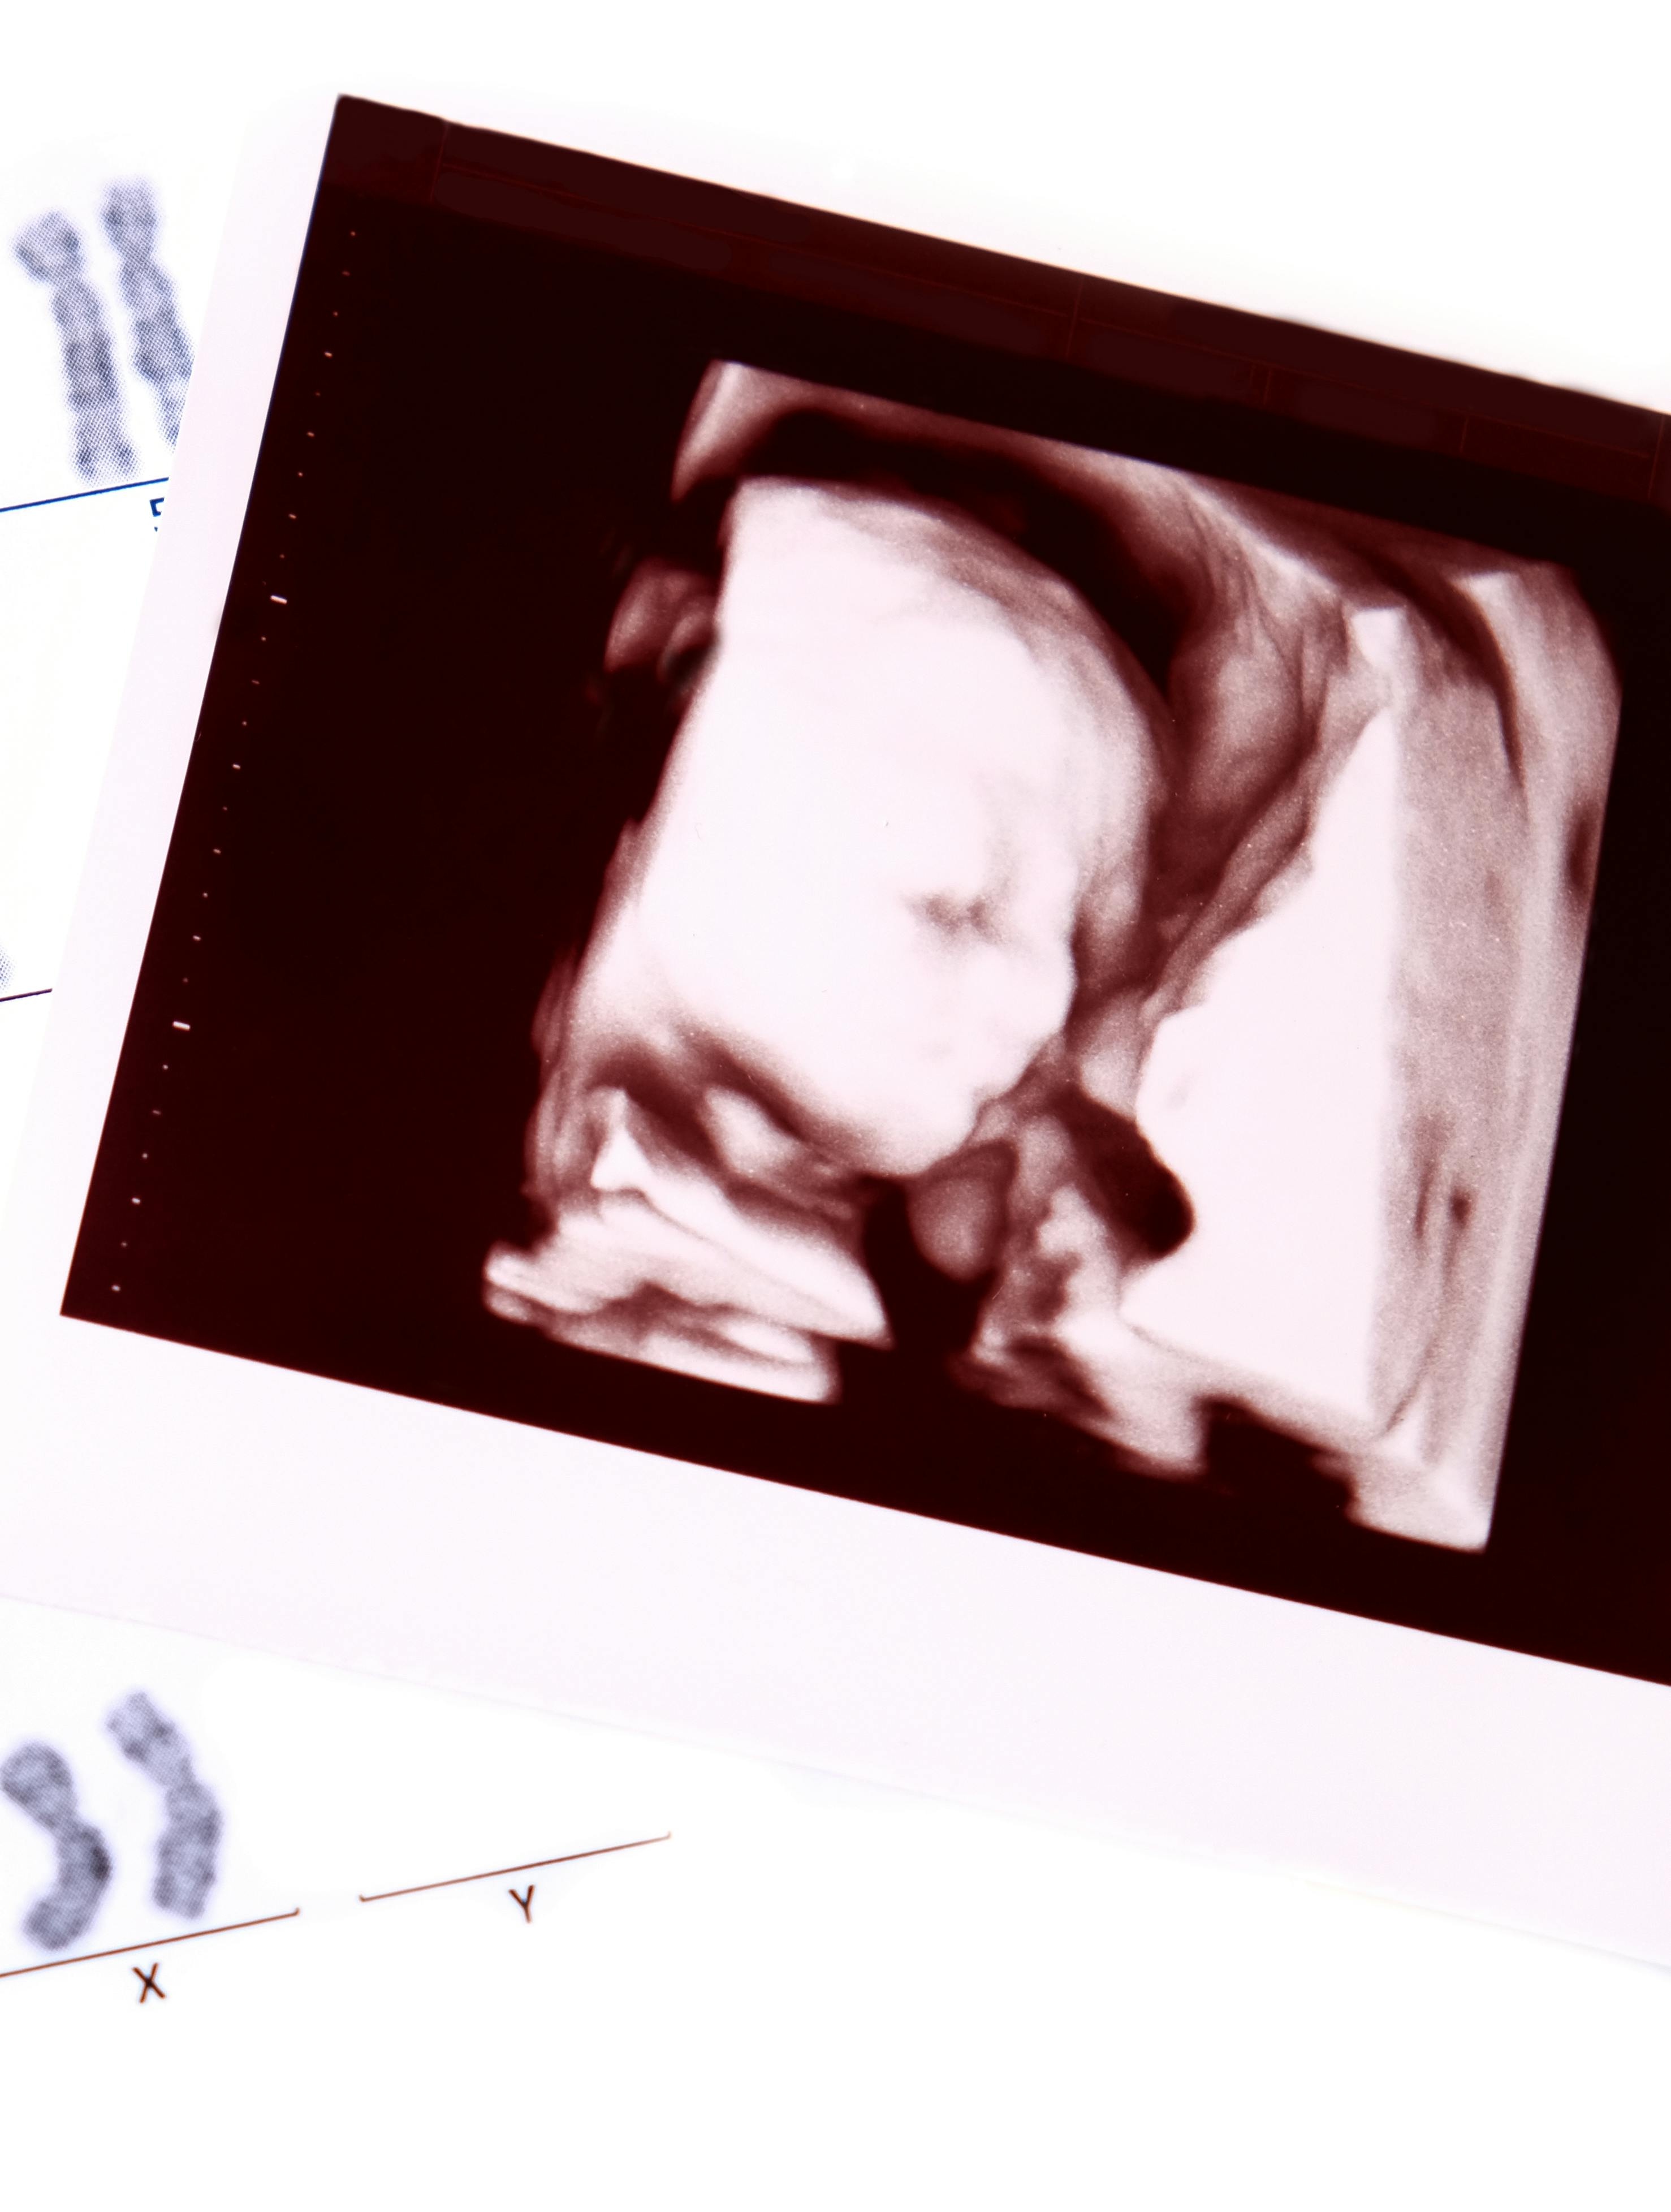

Gravid: Hvorfor vælge en NIFTY test?

En NIFTY test er en risikofri blodprøve fra moderen, der vurderer sandsynligheden for kromosomafvigelser hos det ufødte barn. Ifølge Gravid.dk er denne test særlig nøjagtig for Downs syndrom med over 99 procent nøjagtighed og en meget lav falsk positiv rate på 0,1 procent. Testen kan også identificere sjældnere trisomier og anomalier på kønskromosomer.

Forskellen er metoden; undersøgelsen bliver lavet gennem blodet hos en NIFTY test og gennem ultralydsscanning hos nakkefoldsscanning.

Nakkefoldsscanningen er en ultralydsscanning, der normalt udføres mellem 11. og 14. graviditetsuge. Den måler tykkelsen af fosterets nakkefold og bruges til at vurdere risikoen for visse kromosomale tilstande, herunder trisomi 21 (Downs syndrom), trisomi 18 (Edwards syndrom) og trisomi 13 (Pataus syndrom), samt andre genetiske lidelser.